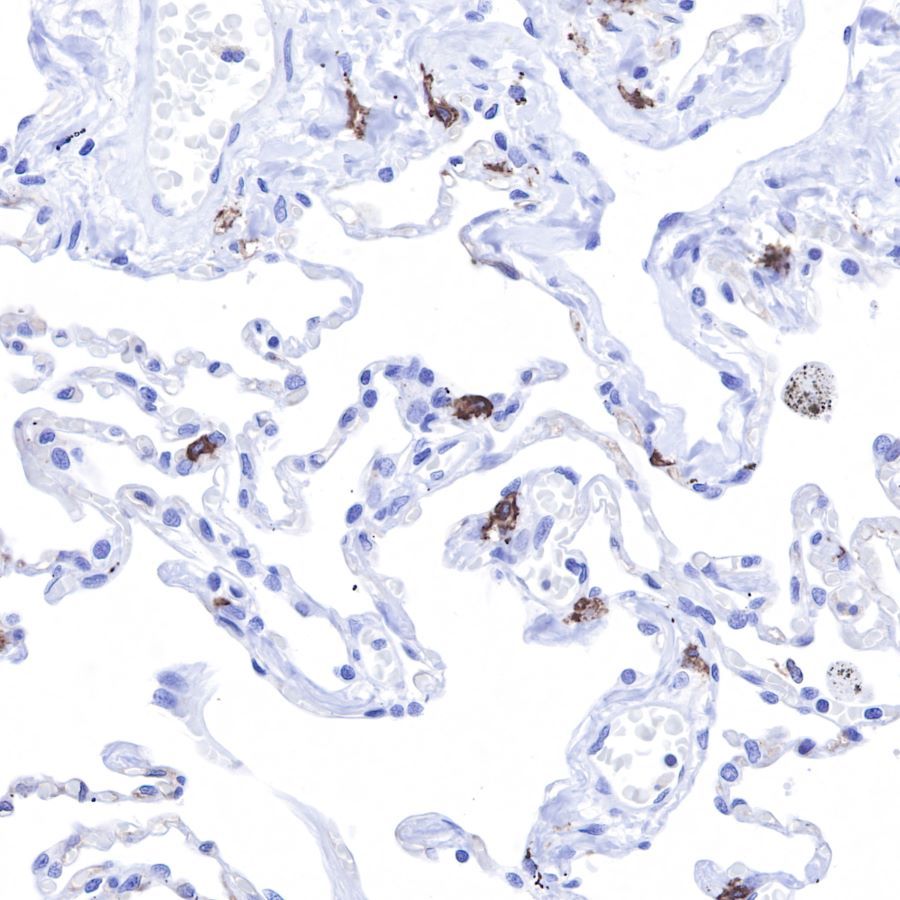

IHC shows positive staining in paraffin-embedded human lung.

Anti-CD117 antibody was used at 1/1000 dilution, followed by a

Goat Anti-Rabbit IgG H&L (HRP) ready to use.

Counterstained with hematoxylin.

Heat mediated antigen retrieval with Tris/EDTA buffer pH9.0 was performed before commencing with IHC staining protocol.